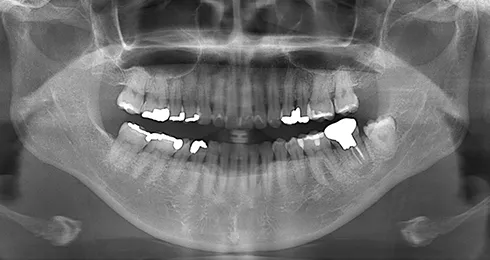

| 年齢/性別 | 50代女性 |

| 主訴 | 左下奥歯に痛みがある、全体的に治したい |

| 治療内容 | 全体的に歯周病やむし歯、根の治療を行い、仮歯を使用して咬合治療を実施。右下2本、左下1本の計3本を抜歯し、その後、右下に2本、左下に2本の計4本のインプラントを埋入しました。 |

| 治療期間 | 8か月 |

| 費用 | 2,106,500円税込 |

| リスク・副作用 | 炎症反応によって術後に腫れが生じることがあります。その程度は、手術の範囲や方法によって異なりますが、多くの場合、時間の経過とともに徐々に治まります。 ごく稀に、下顎奥歯の外科手術後に、唇や顎に痺れを感じることがあります。 |